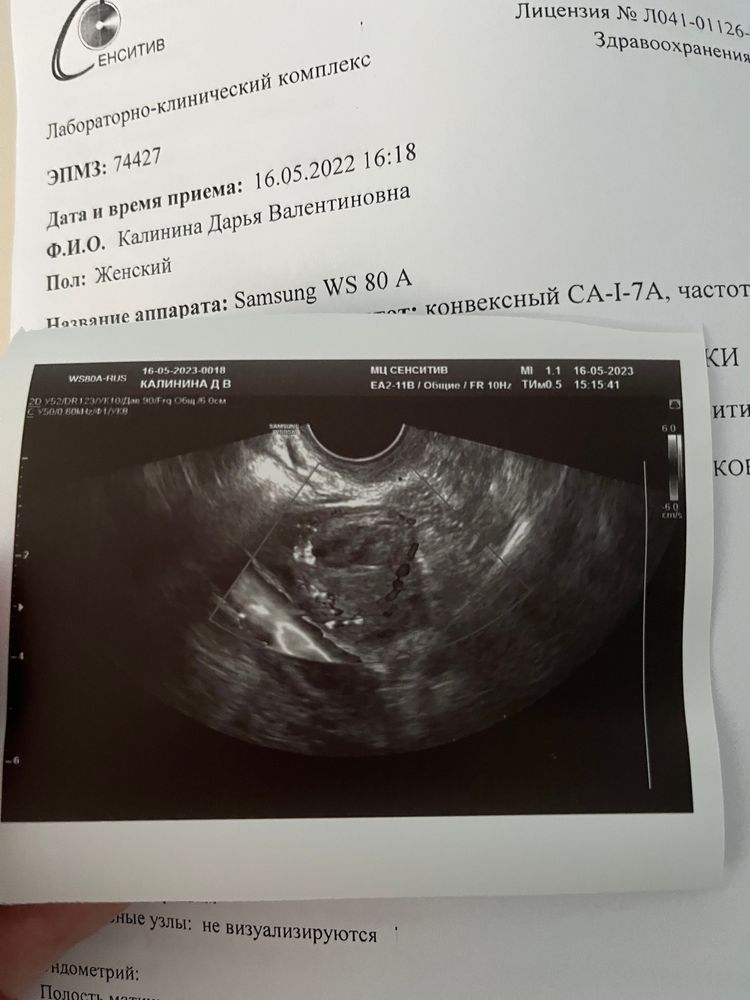

Первая победа, овуляция свершилась!

Овитрель + Декапептил Стимуляция Летрозолом